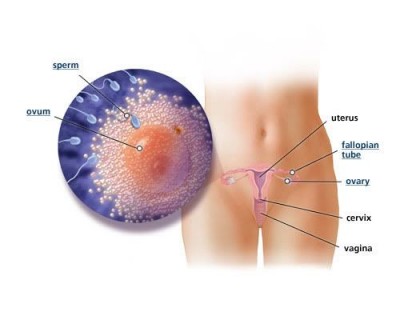

Вагітність починається з моменту запліднення або зачаття. Це складний комплекс біологічних процесів злиття жіночої і чоловічої клітин, з'єднання їх генів в одну нову клітку, яка і являє собою новий дочірній організм.

Процес запліднення відбувається у верхній частині маткової труби. Запліднення жіночої яйцеклітини відбувається одним, рідко двома спермиями. Для того, щоб процес цей стався, необхідно, щоб в організм жінки потрапили 60-100 млн чоловічих клітин. Інакше вірогідність зачаття знижується.

Існує два типи сперміїв, залежно від що міститься в них статевої хромосоми: У - чоловіча хромосома і Х - жіноча. Вважають, що спермії, що містять У-хромосому, більш швидкі і живуть більш коротке життя, ніж спермії, що містять Х-хромосому. Тому ймовірність зачаття хлопчика буде більше, якщо статевий акт стався в момент овуляції - виходу зрілої яйцеклітини, що відбувається на 12-16 день менструального циклу. А якщо він був до овуляції за кілька днів, то все спермії, що мають У-хромосому, гинуть, і з'являється більше шансів зачати дівчинку.

Запліднена яйцеклітина рухається по матковій трубі в порожнину матки. Рух зародка триває три доби. Характер і час його «подорожі» багато в чому визначають подальший розвиток зародка. Якщо перистальтика труби уповільнена, то може виникнути позаматкова вагітність. Це може статися у жінок з запальними захворюваннями жіночих статевих органів, що мали аборти до цієї вагітності, з пороками розвитку матки. Якщо рух зародка занадто швидке, це також порушує нормальний розвиток вагітності, т. К. Зародок надходить в матку в тій стадії розвитку, коли не може відбутися його приживлення. Або воно відбувається в нижніх відділах матки, тобто в місці, менш підходящому для подальшого розвитку плода, і це дає важке ускладнення вагітності - передлежання плаценти. Таке може трапитися у жінок з гормональними порушеннями і з пороками розвитку матки.